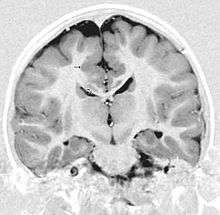

Like focal subcortical heterotopia, "band" heterotopia form in the white matter beneath the cortex, but the gray matter is more diffuse and is symmetric between the hemispheres. On imaging, band heterotopia appears as bands of gray matter situated between the lateral ventricle and cerebral cortex and separated from both by a layer of normal appearing white matter. Band heterotopia may be complete, surrounded by simple white matter, or partial. The frontal lobes seem to be more frequently involved when it is partial. Patients with band heterotopia may present at any age with variable developmental delay and seizure disorder, which vary widely in severity.

Subcortical band heterotopia, also known as “double cortex” syndrome, refers to a band of subcortical heterotopia neurons, located midway between the ventricles and the cerebral cortex. The disorder is seen primarily in females and typically causes varying degrees of mental retardation and almost all of them have epilepsy. Approximately two thirds of patients with epilepsy ultimately develop intractable seizures. MRI of the brain in subcortical band heterotopia demonstrates two parallel layers of gray matter: a thin outer ribbon and a thick inner band, separated by a very thin layer of white matter between them. The severity of epilepsy and developmental delay is directly correlated with the degree of migration arrest,as indicated by the thickness of the subcortical band heterotopia.